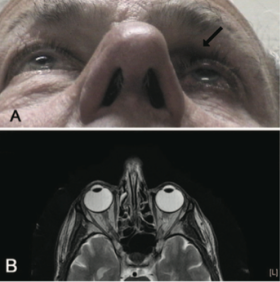

Imaging is not commonly done and is not usually indicated in patients suspected to have Prostaglandin Associated Periorbitopathy. However, often times imaging is performed in patients on unilateral therapy to rule out pathology of the contralateral eye. In this situation, CT or MRI of the orbits can reveal a difference in globe position of the two eyes with the treated eye often situated more posterior in the orbit, as well as a more apparent kinking of the optic nerve of the treated eye representing different axial positions of the two globes. Finally, it is possible to see relative lateral rectus laxity in the treated eye due to orbital fat volume depletion (See Fig 11, 12).

Fig 12: Patient initially presenting for 1 month of intermittent binocular diplopia with history of bimatoprost use in the left eye for 7 months. MRI brain, orbits and MRA head and heck were all performed, which were normal other than apparent enophthalmos and a kinking of the left optic nerve. Courtesy of Filippopoulos et al.